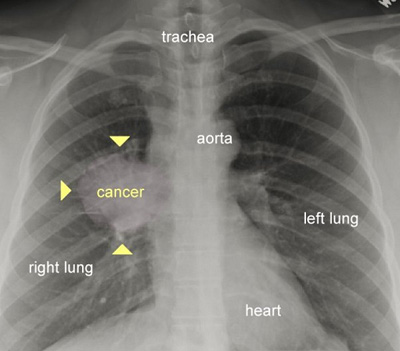

سرطان ریه

در این تصویر نقطه سرطانی در ریه به خوبی قابل مشاهده است. یک ریه سالم فاقد هر گونه تاری یا نقاط بزرگ است.